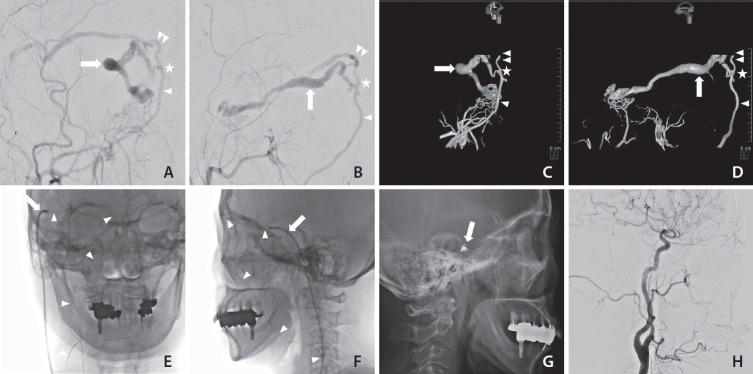

Management of cavernous sinus dural arteriovenous fistula (CSDAVF) continues to present significant challenges, particularly when the inferior petrosal sinus is thrombosed, collapsed, or angiographically invisible. In this study, we introduce facilitated retrograde access via the facial vein, which is employed in the transvenous embolization of CSDAVF with isolated superior ophthalmic venous drainage. We also present illustrative cases and technical points.